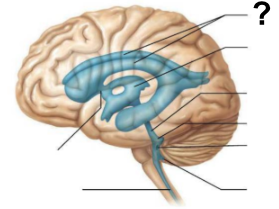

What structure, labeled “?”, is the starting point of cerebrospinal fluid circulation in the brain?

Lateral ventricle